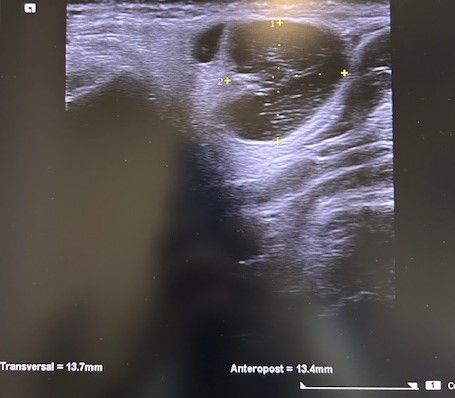

Eco-PAAF: lesión sólida de morfología nodular posterior al ángulo mandibular derecho, con medidas aproximadas de 15 x 21 mm. Presenta ecoestructura heterogénea con áreas quísticas en su interior y con vascularización en el estudio Doppler.